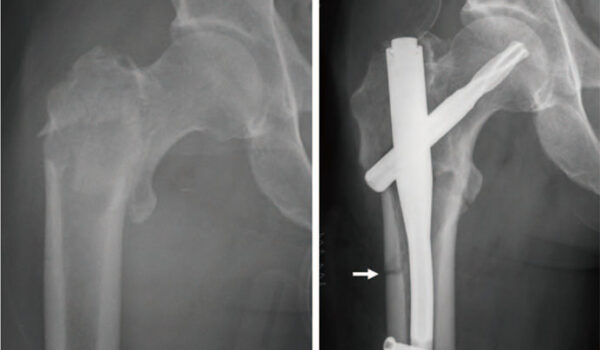

مراقبت‌های بعد از عمل شکستگی اندام تحتانی (Nail)

به دلیل استفاده از نیل در عمل شما، ترخیص طی حداکثر دو روز بعد از عمل انجام خواهد گرفت. در طول مدت بستری مراقبت از زخم ناحیه عمل شما بنابه صلاح‌دید انجام می‌شود. این مدت زمان برای پایش عوارض زودرس احتمالی بعد از عمل ضروری است. مسلماً در صورت بروز عوارض مدت بستری افزایش خواهد یافت.